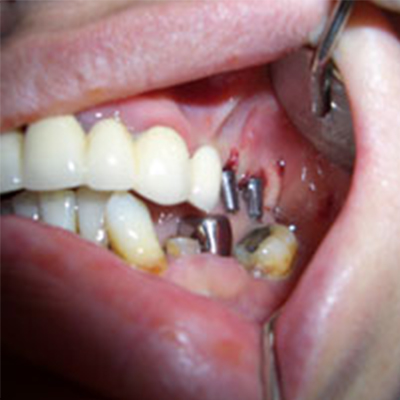

Replacement of several teeth

If you have lost several teeth, replacing them with dental implants is an excellent alternative to bridges or partials because your replacement teeth are not dependent on support from adjacent teeth and do not require the inconvenience of a removable appliance. Below are some examples of patients who chose dental implants to restore multiple missing teeth.